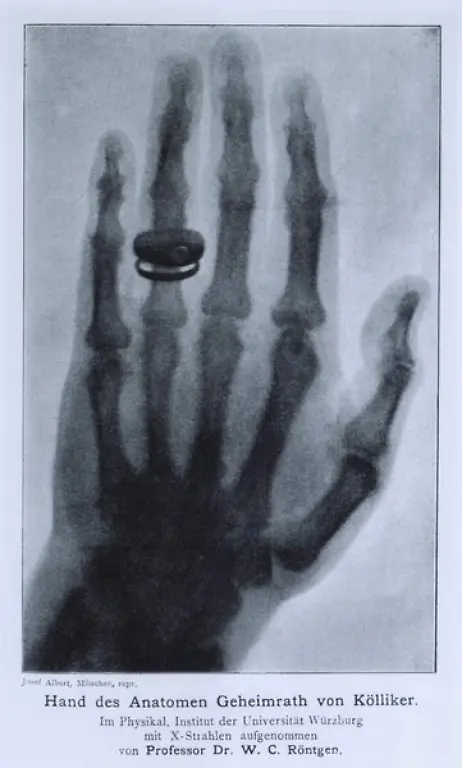

Er war ein Revolutionär der Medizintechnik: Der Physiker Wilhelm Conrad Röntgen entdeckte 1895 zufällig die X-Strahlen, was nicht nur für die Diagnostik in der Medizin ein Meilenstein war. Später wurden die Strahlen und das Verfahren nach ihm benannt. Röntgen starb vor 100 Jahren in München.